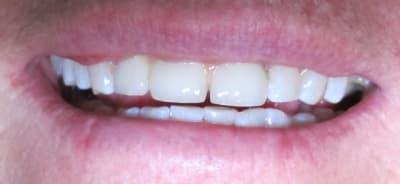

La 21 a été retouchée après la photo

Pas emballé. L'esthétique est certes sympathique, mais il sera absolument impossible pour le patient d'assurer une hygiène correcte là-dessous. Paro à prévoir de manière rapide...

Cas d'implant pour moi (et quand je dis pour moi, c'est pour mon correspondant).

Si vraiment on se tourne vers le bridge, pourquoi pas élongation coronaire 21, ce qui aurait permis de fermer le diastème de manière plus conventionnelle...